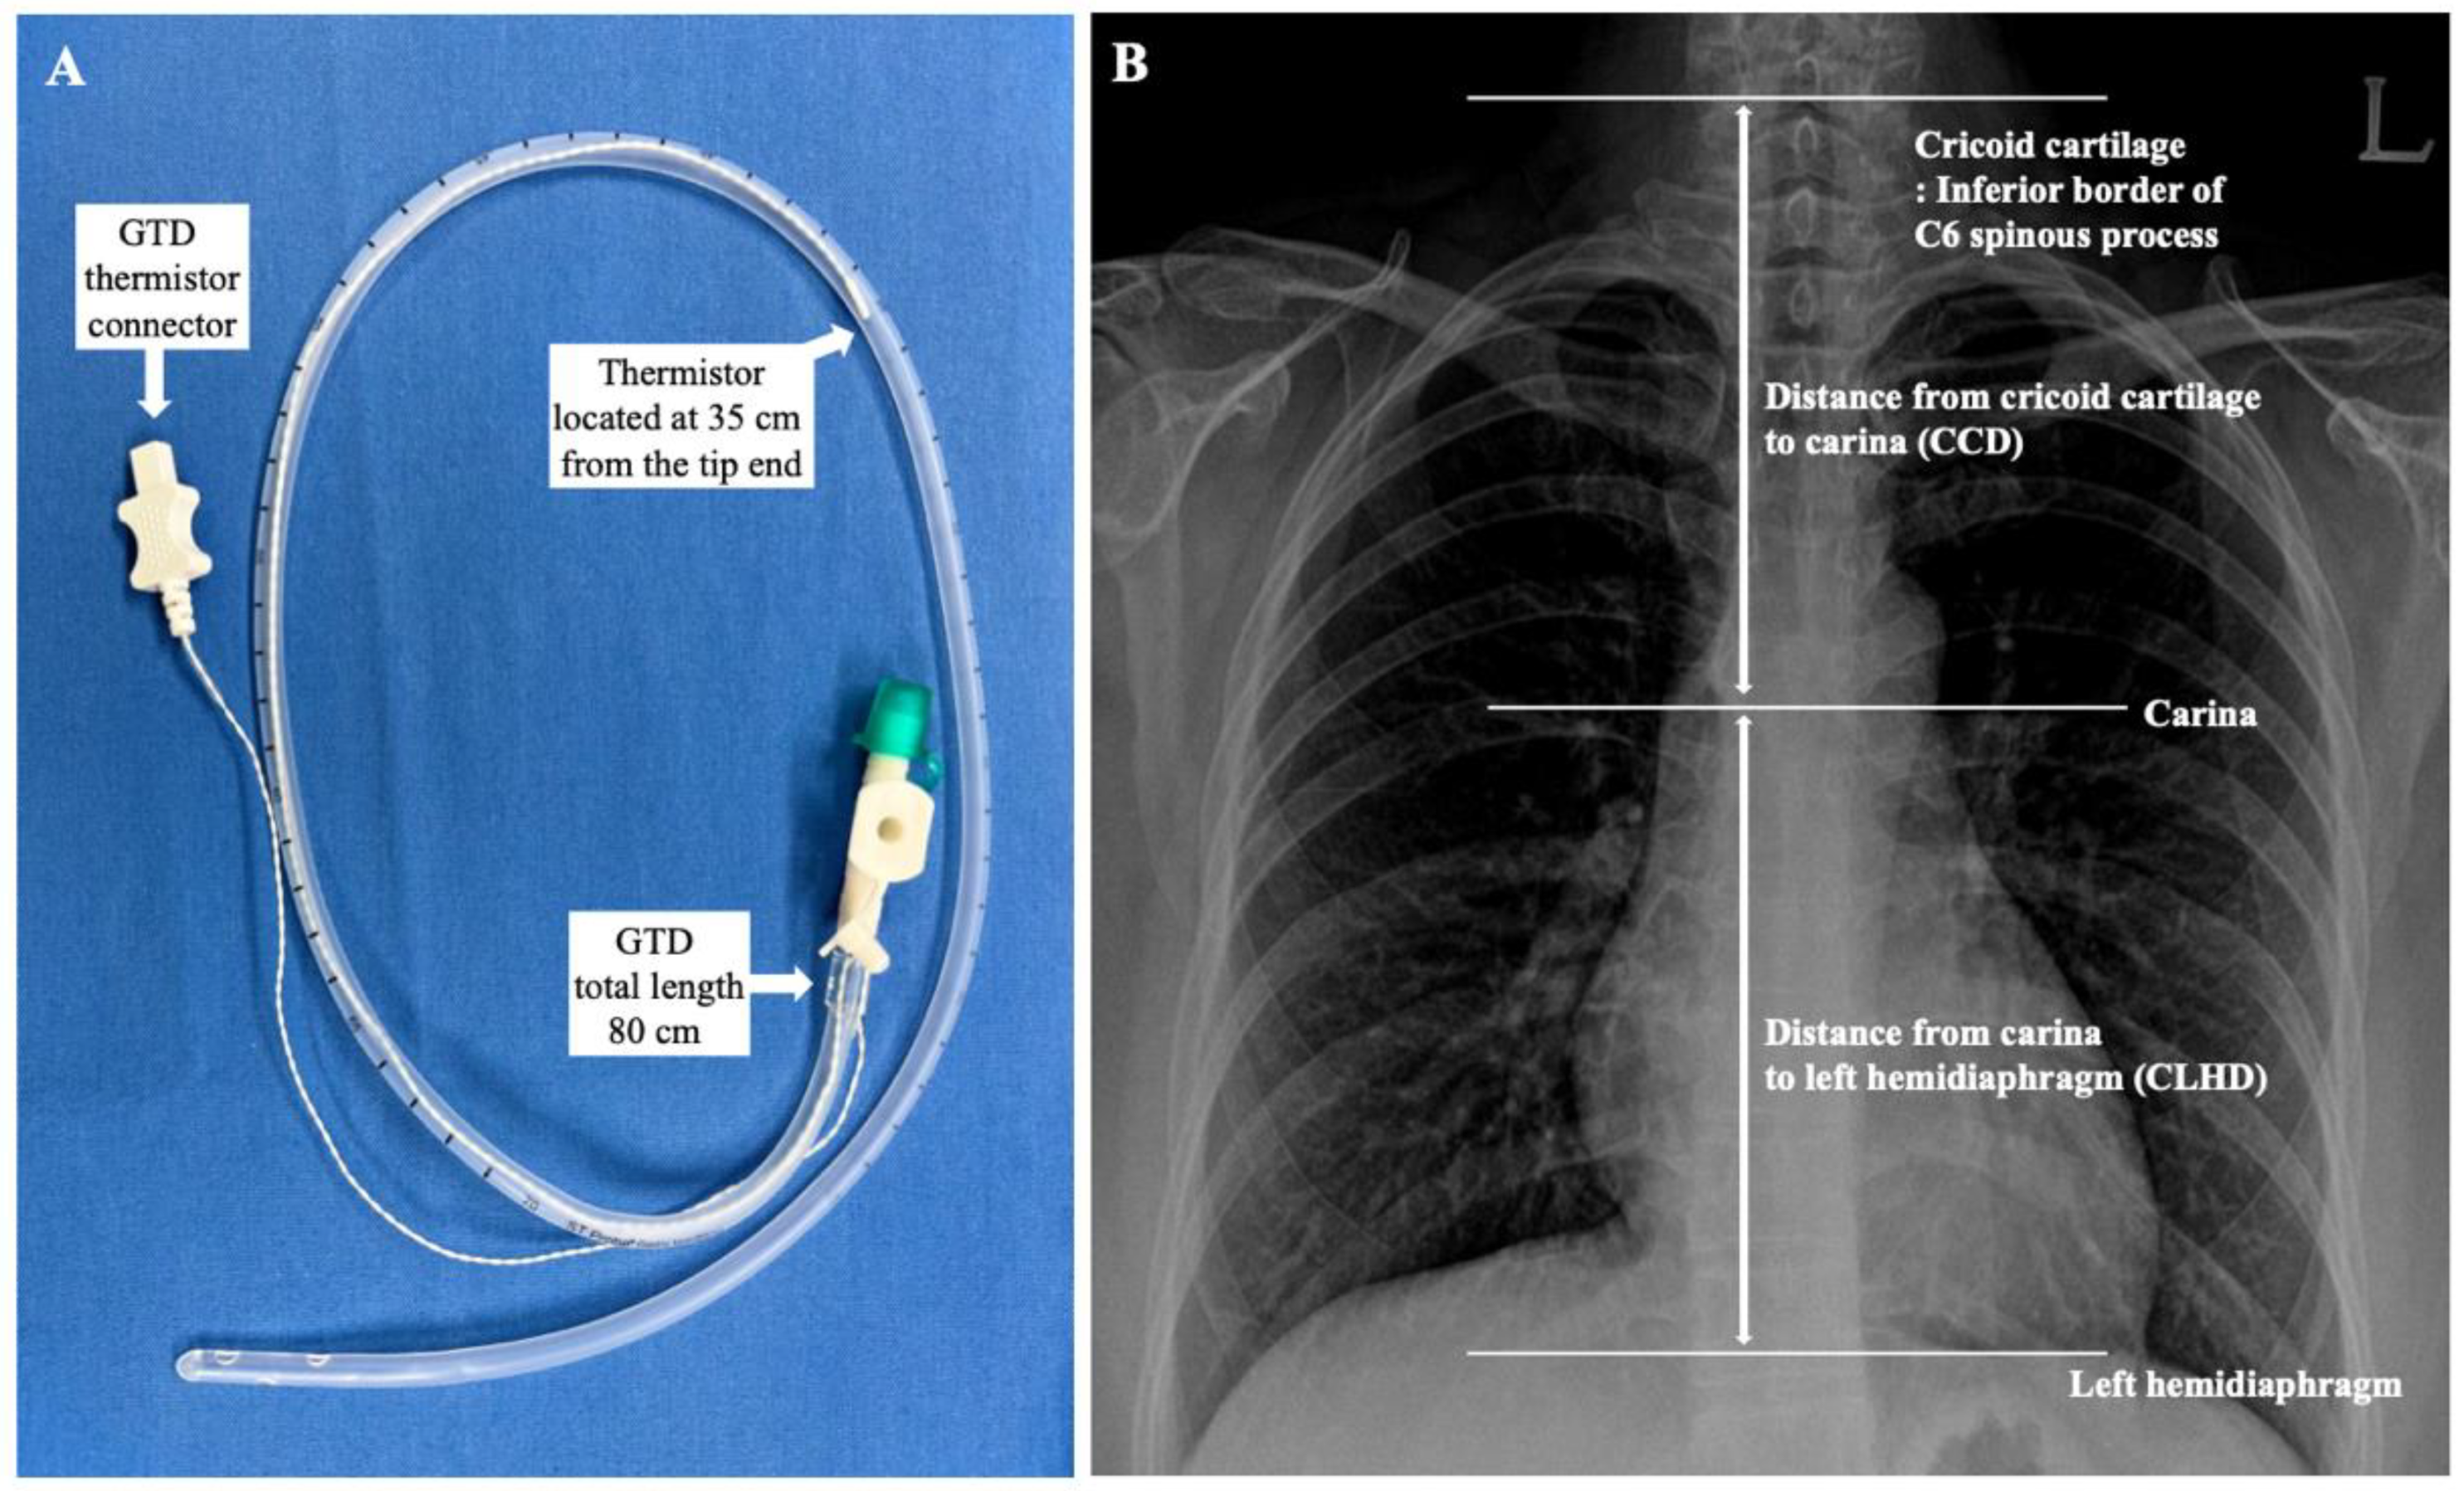

Core temperatures were measured with a tympanic thermometer (Thermoscan IRT 4020, Braun, Kronberg, Germany). When the TM temperature was constant after measuring three consecutive times at 10-s intervals, the temperature was assumed as the core body temperature. The GDT with a temperature probe (ST probe, S&S MED, Gunpo, Korea, Figure 1A) sized 18 Fr. (total length of 80 cm) was inserted carefully by the trained anesthesiologist and confirmed by ultrasound (M-Turbo®, Fujifilm Sonosite, Inc, Bothell, WA, USA) and video-laryngoscopy [19]. The reference insertion length of the GDT was estimated for each patient using the conventional nose–earlobe–xiphoid distance (NEX) method [20,21]. Initially, the GDT was inserted from the nose to a depth of NEX + 12 cm. However, if the NEX + 12 cm was longer than 80 cm, the initial insertion depth was started from 80 cm because the total length of the GDT was 80 cm. Finally, each probe was connected to the clinical monitor and recorded temperatures.

Thirty minutes after Trendelenburg positioning of patients for the surgery and initiation of pneumoperitoneum, when the changes in the body temperatures stabilized, initial temperatures of the TM and GDT thermistor were assessed. After 5 min, the GDT was withdrawn 2 cm, and the temperatures of each site were measured when the temperature change of the GDT thermistor stabilized below 0.1 °C. Eventually, the depth of the GDT was changed from NEX + 12 to NEX − 12 cm with a 2-cm interval, and the temperature at each position was measured. At the same time, the core body temperatures of the TM were measured and compared with the temperature of the GDT thermistor. For the further evaluation of the optimal insertion depth of the GDT, anatomical landmarks, such as distance from the cricoid cartilage to the carina (CCD) and distance from the carina to the left hemidiaphragm (CLHD), were measured using an electronic caliper on a CXR of each patient (Figure 1). Since the cricoid cartilage is located at the level of the C6 spinal vertebrae [22], the inferior border of the spinous process of the C6 vertebrae was assumed to be the level of the cricoid cartilage.

Figure 1. (A) Gastric decompression tube (GDT). The total length of the tube was 80 cm, and the thermistor was located at 35 cm from the end of the GDT tip. (B) Assessment of anatomical landmarks on chest X-ray.